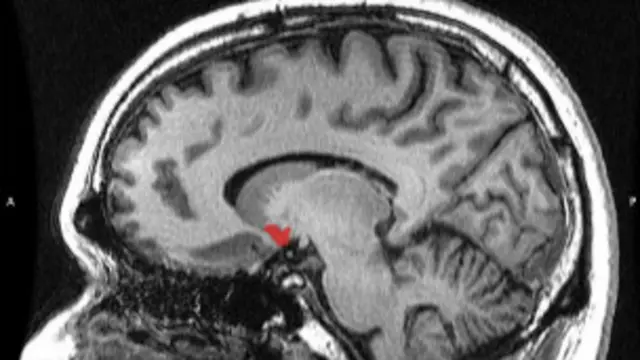

Durante sua pesquisa, Komisaruk colocou suas pacientes em câmaras de ressonância magnética com a recomendação de estimular suas partes íntimas até alcançar o orgasmo.

O monitoramento cerebral desse processo o levou a algumas conclusões interessantes, que Komisaruk compartilhou nesta entrevista telefônica com a BBC Mundo, o serviço em espanhol da BBC.

Komisaruk - Monitoramos sua atividade durante o clímax e observamos quais zonas são ativadas quando a mulher tem um orgasmo. Já vimos que seus efeitos benéficos chegam a todos os sistemas principais do cérebro. Eu me refiro ao sistema sensorial, ao sistema de coordenação motora, etc.

Komisaruk - É precisamente isso que queremos comprovar. Para isso, permitimos que a paciente veja a própria análise de seu cérebro ao vivo. Estamos no processo de averiguar se visualizar os processos de nossa mente ajuda a controlá-la. Há uma zona chamada núcleo accumbens que é a área do prazer.

Essa área é ativada pela nicotina, pelo chocolate, pela cocaína e também pelos orgasmos. A minha pergunta é: podemos ensinar a nós mesmos como aumentar conscientemente a atividade nesse núcleo observando seu funcionamento? Que efeito teria isso em pacientes com depressão ou ansiedade?